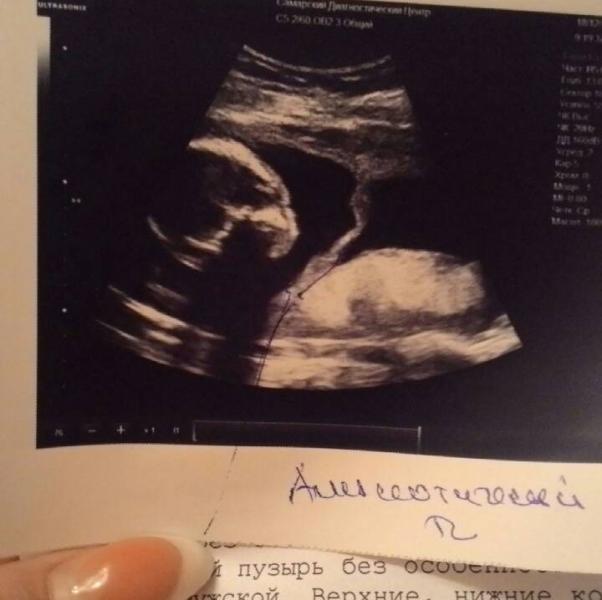

Наша 37 неделька с малышкой)😄

Начну с плохого: была на консультации с акушером в 4ке. Честно говоря после разговора приехала расстроенная😯. При осмотре сказала многоводие (хотя в 31 неделю мне такого не ставили), при осмотре высоты дна матки у нее вышло 33 см (хотя сегодня была в своей жк 38), еще и впервые услышала, что у меня узкий таз. Ее выводы: многоводие, задержка плода, малоразмерный плод (хотя на узи в 31 неделю малышка весила 2 кг), старение плаценты??? Срочно на узи.

Девчата! Всем привет !!!! Был у меня сегодня 2 скрининг в Диагностическом центре на Мяги ! Как я волновалась это ужас!!! Слава Богу все хорошо с малышом! Нам также сегодня сказали пол ! Я выкладывала недавно пост о том как муж посмотрел на живот и сказал там мальчик !!! Так вот у нас СЫН !))) Хотя в СШУ на 15,2 делали узи и там сказали девочка 70 % ))) Вобщем мы счастливы оба !!! Единственное у меня в полости матки амниотический тяж... то по такая перетяжка которая делит матку пополам...буду на...